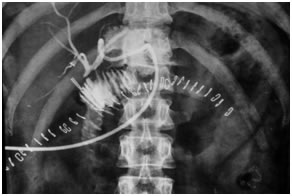

CT Scan showing Lipoidol uptake in segment VIII